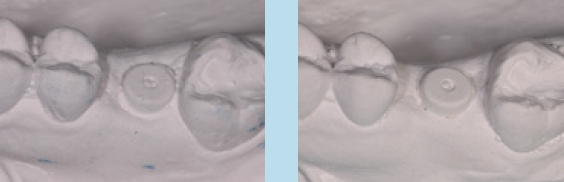

Unabhängig, ob digital oder analog vorgegangen wird, ist bei der Einbringung der Abformpfosten bzw. Scanbodies darauf zu achten, dass diese sich nicht berühren oder die Nachbarzähne touchieren. Liegen Freilegung und Implantation zeitlich weit auseinander und wurde die Lücke nicht provisorisch versorgt, kann es zum Aufwandern der Nachbarzähne kommen (Abb. 14–17). In diesem Fall ist es notwendig, die Abformpfosten zu beschleifen oder das Aufwandern kieferorthopädisch zu behandeln.

Cave: Veränderungen an den Okklusalflächen durch provisorische Füllungen oder Kronen bei fehlendem Lückenersatz können zu Zahnbewegungen in die Lücke führen. Das Tragen eines nächtlichen Retainers in Form einer Miniplastschiene kann dies verhindern.